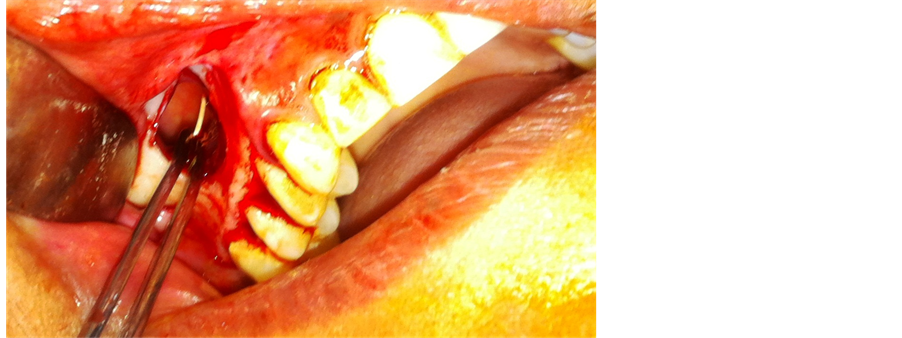

An elliptical incision was made in the right upper molar region, the epithelial tract with inflammatory tissue was completely excised, and two divergent incisions were extended into the vestibule. The trapezoidal buccal mucoperiostal flap was reflected from the alveolus and the lateral wall of the maxilla a window was made in lateral wall of maxillary sinus, the sinus lining was gently elevated till the GP was visible (Figure 2). The buccal fat pad was exposed through a 1 cm vertical incision through the periosteum posterior to the zygomatic buttres (Figure 3). The fat pad was gently advanced over the bony defect, and secured with sutures (Figure 4) after removing the gutta percha point (Figure 5). The mucoperiostal flap was replaced in its original position and sutured. After 10 days follow up, the surgical site was completely healed with no complications (Figure 6).

Figure 2. Gutta percha clearly visible in the right maxillary sinus through the Caldwell-Luc approach.